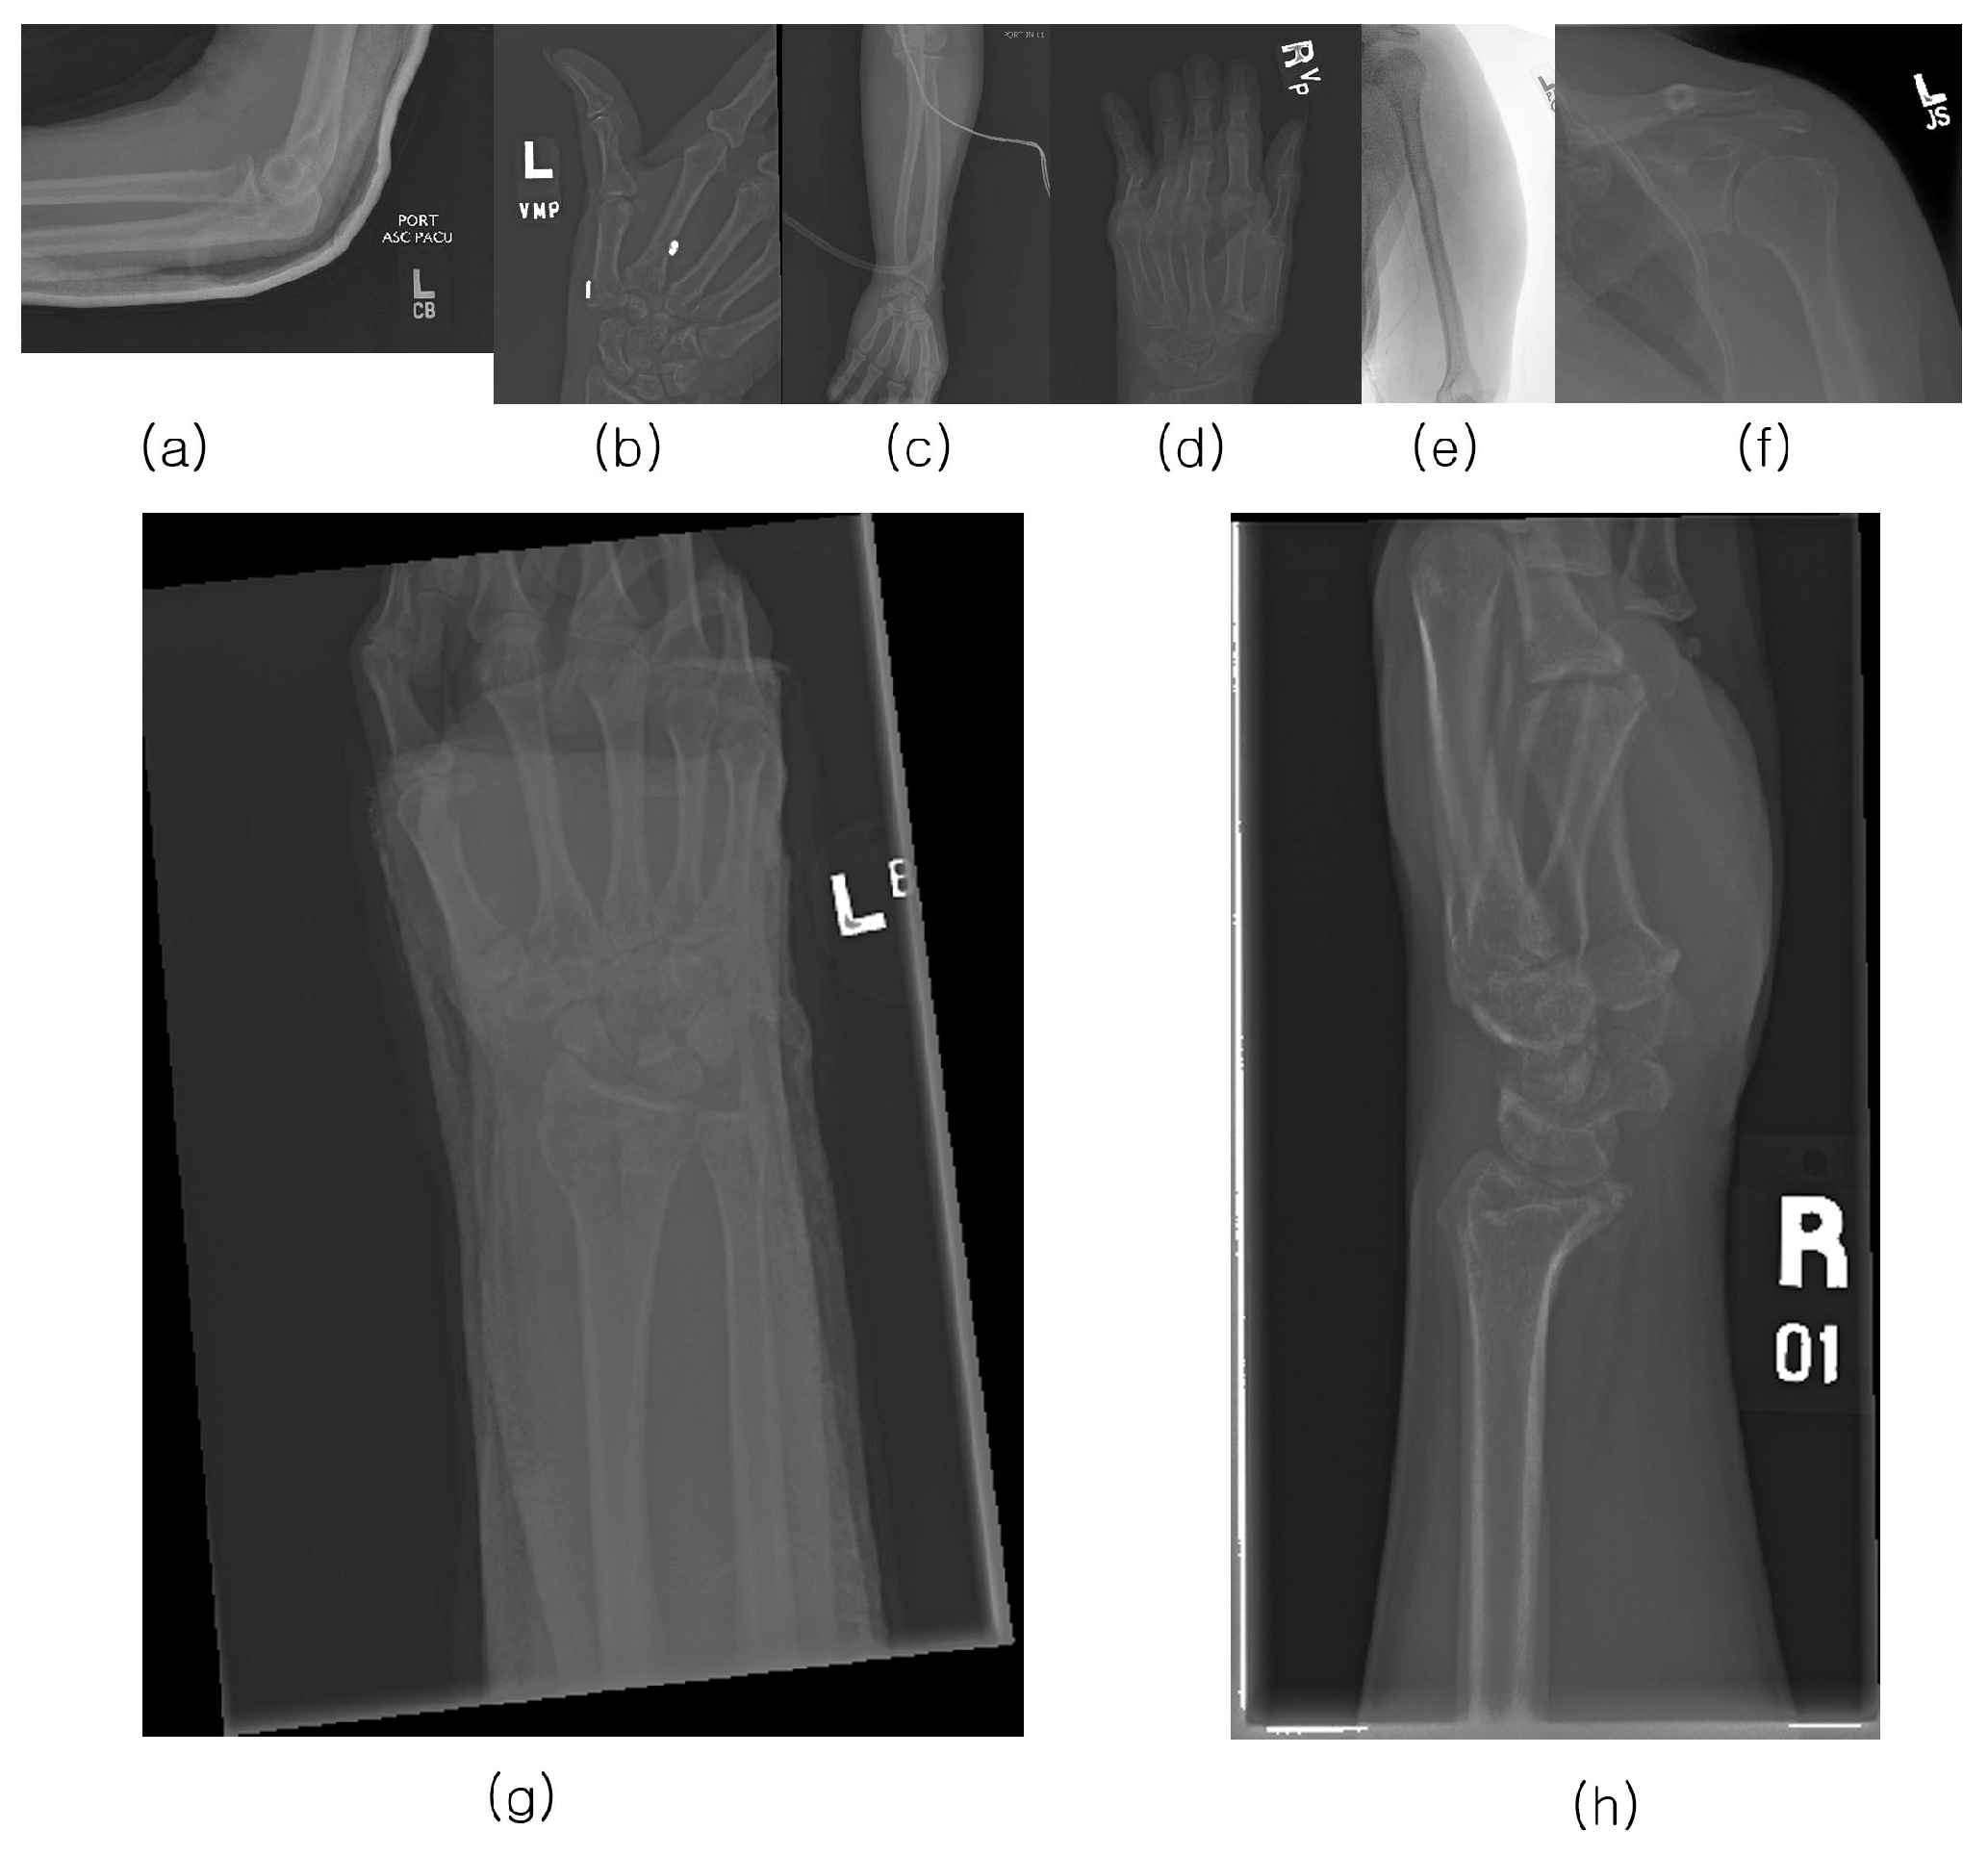

The GRAZPEDWRI-DX dataset consists of 6091 pediatric trauma wrist radiographs treated at the Department of Pediatric Surgery, University Hospital Graz, between 2008 and 2018. In total, 74,459 image tags were assigned to the 20,327 images. These tags included bone anomaly, bone lesion, foreign body, fracture, metal, periosteal reaction, pronator sign, soft tissue, text, and centerline. Of these, 18,090 boxes were marked as fractures, and 13,550 images had one or more fracture boxes. These were reviewed at least twice by a pediatric radiologist. The authors made the data publicly available. Figure 2 shows an example of multiple bounding boxes in one of the GRAZPEDWRI-DX datasets.

Figure 2. GRAZPEDWRI-DX dataset with the red box indicating the ground truth fracture region.